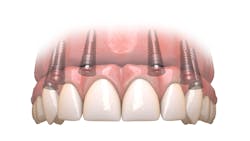

As a prosthodontist who has spent the last 25 years offering full-arch treatment to my patients and teaching the Hybridge full-arch protocols for most of that time, the phrase “Pick a Path” has come to refer to the difficult decision a patient makes to either commit to restoring their natural dentition or to replace their remaining teeth with a completely implant-supported prosthesis, as in a full-arch solution. The last decade has seen this implant modality gain in popularity.

Today, more than ever, patients expect and hope their dental restoration will solve what has historically been a lifetime cycle of dental problems and expense. In this case, a straightforward, conventional restorative treatment plan that focuses on restoring the patient’s natural teeth may not make the most sense long term. After comparing both restorative paths, the full-arch implant option would likely prove to have a better prognosis, lower cost, and require much less time and fewer appointments.